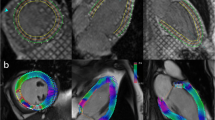

Echocardiography and cardiac MR data were analysed for principal myocardial strain (Fig. 1). Analysis was performed on all available long axes orientations in both modalities as well as a single mid-ventricular short axis location. To ensure comparable short axis slice locations for both echocardiography and MRI data, two readers selected the appropriate mid-ventricular slice based on a comparative review of anatomical features (LV/RV trabeculations, moderator band and papillary muscles) in a consensus setting. Subsequently data were assessed for longitudinal strain (Ell) as well as circumferential (Ecc) and radial (Err) strain. Peak systolic global longitudinal strain (GLS), global circumferential strain (GCS) and global radial strain (GRS) data are reported for both modalities using Lagrangian strain priniciples.

MR deformable registration analysis

Inverse DRA was performed using a prototype automated segmentation tool programmed in Visual C++ (Trufi Strain, Siemens Healthcare, Medical Imaging Technologies, Princeton, NJ, USA). The software automatically identifies anatomical landmarks such as the mitral valve points and apex point on long axis slices and the RV insertion points and lateral point on short axis images. The software subsequently automatically delineates endo- and epicardial myocardial borders on short axis data sets [26, 30]. In order to ensure temporal consistency of the endo- and epicardial contours, the segmentation algorithm relies on a deformable registration algorithm that calculates dense deformation fields between any two frames in a slice. After a contour is identified in one frame, it is automatically propagated to the other frames in the slice [27].

Analysis of long axis strain followed a semi-automated approach with the observer drawing an initial endocardial and epicardial contour on diastolic frames of all three available long axis orientations without further corrections. Processing was then automatically performed with propagation of these contours to all other frames using the same deformable registration algorithm [27].

Deformation fields calculated for the purpose of contour segmentation can directly be used to calculate strain values inside the myocardium because the Lagrangian strain tensor can directly be expressed in term of the gradients of the displacement fields (online appendix) (Figs. 2 and 3). All results were exported for data analysis.